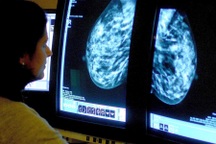

Theo đó, phụ nữ trên 40 tuổi nên tầm soát ung thư vú bằng siêu âm tuyến vú hoặc chụpmamographyy 1 năm/ lần.

Với những phụ nữ có yếu tố nguy cơ cao mắc ung thư vú việc tầm soát cần được thực hiện sớm hơn, nên siêu âm tuyến vú, chụpmamographyy và chụp cộng hưởng từ tuyến vú 1 năm/ lần.